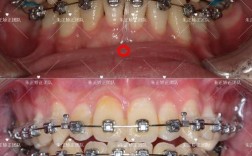

(图片来源网络,侵删)- 希望改善因牙齿问题导致的面部轮廓不协调(如嘴凸、瘪嘴、下巴后缩或前突、面部不对称等)。

(图片来源网络,侵删)对于替牙期(混合牙列期)的儿童,某些问题(如严重的牙列拥挤、不良习惯导致的错颌、骨性问题如上颌前突/后缩、下颌偏斜等)需要早期干预,引导颌骨和牙齿向正常方向发育,避免问题恶化,简化后续治疗难度。